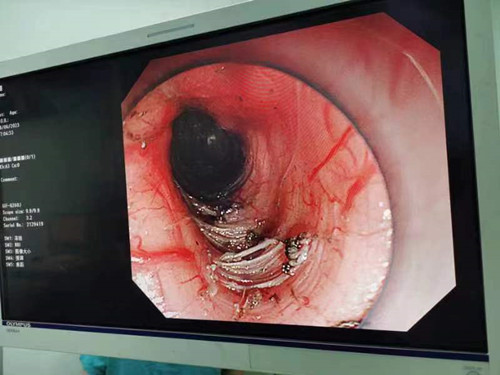

近日,消化内科二病室先后入住了两位患者,因为“进食哽咽感”来寻求治疗。想吃东西,胃“不开门”,怎么办?两位患者入住后做了消化道钡餐检查,结果显示“食管下段呈鸟嘴样改变”,确诊为贲门失迟缓症。确诊后,吴明浩主任为患者进行POEM手术——切开食管环状肌,为患者打开食管与胃的“大门”,以达到缓解症状的效果。手术两天后,患者开始逐渐进食,“我现在能一次性吃下一碗粥都不会觉得堵了”一位患者术后开心地告诉护士,比起术前,一碗粥药分好几次喝,喝一点就会觉得前胸有梗阻感,现在能顺利进食的感觉太好了。

吴明浩主任介绍,贲门失弛缓症是一种原因不明的食管括约肌松弛障碍和食管体部无蠕动为主要特征的原发性食管动力紊乱性疾病。临床常见症状为:吞咽困难、食物反流以及下段胸骨后不适或疼痛,可伴有体重减轻甚至营养不良,严重影响患者的生活质量。一般来说,通过口服药可以松弛食管下段肌肉的紧张度,但是这种方法对于很多患者并不十分有效。POEM手术是目前治疗贲门失迟缓安全、有效的一种方式,内镜经口进入食管到达贲门,不需要外科手术开胸,体表无手术创伤,术后恢复快速,并发症少。小小的手术,便能打开胃的“大门”,缓解患者的症状,让患者畅快地进食。(消化内科二病区 曾皓 曾敏婕)